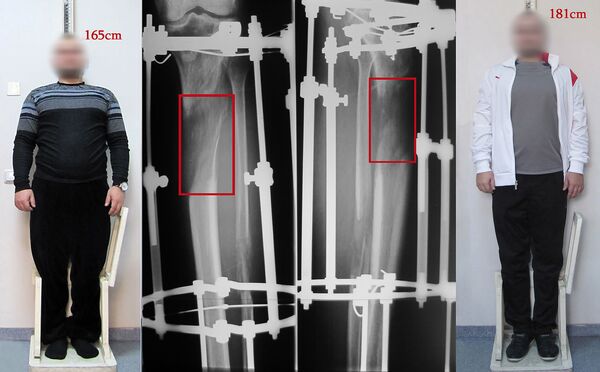

Японец Маебара Кеичи — один из немногих, кто решился радикально изменить свою жизнь и навсегда избавиться от комплекса "маленького человека": в прямом смысле – не в гоголевском. А помогли ему в этом армянские врачи, увеличив его рост на целых 10 сантиметров.

Все началось с поискового запроса в Google об операциях по увеличению роста. В отзывах прочитал, что ее очень качественно и по доступной цене делают в Армении. Вопрос рискнуть или нет уже не стоял, и в прошлом году Кеичи приехал в Ереван, записавшись на прием к руководителю Ереванского центра реконструкции и удлинения конечностей, травматологу-ортопеду, доктору медицинских наук, профессору Аршаку Мирзояну.

"Под влиянием механического натяжения при помощи аппарата, кость и мягкие ткани растут. Причем рост этот во многом похож на естественный", — коротко объясняет сложнейшую процедуру Мирзоян.

Однако в последнее время лечение по илизаровской методике стали совмещать с методом аппарат/гвоздь, разработанным американскими коллегами. Такая комбинация позволяет значительно сократить сроки лечения. А специфика его в том, что когда конечность достигает необходимой длины, аппарат Илизарова снимают и вставляют внутрикостно специальный стержень (гвоздь). Если раньше курс лечения при удлинении на 10 сантиметров доходил до 12 месяцев, то сегодня достаточно и четырех-пяти.